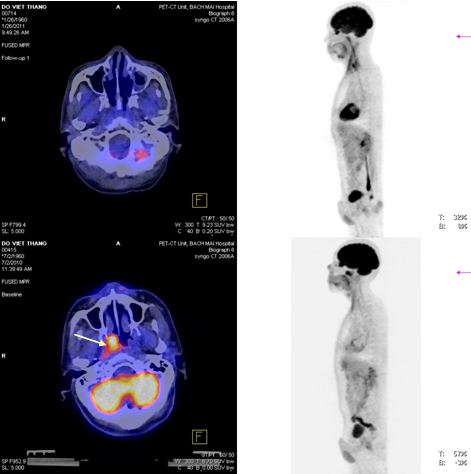

Trước điều trị: khối u vòm lớn tăng hấp thu FDG mạnh.

Sau điều trị: u tan hết, không thấy tổ chức tăng hấp thu FDG vùng vòm.

Hình 8: Bệnh nhân Trịnh Thị Thúy L., nữ, 44 tuổi, vào viện vì đau đầu, chảy máu mũi, được chẩn đoán là K vòm T2N1M0, UTBM không biệt hóa. Được điều trị: PET/CT mô phỏng lập kế hoạch xạ trị IMRT (7 trường chiếu, 43 segments). Sau điều trị hết đau đầu và chảy máu mũi.

Trước điều trị: khối u thành vòm trái tăng hấp thu FDG mạnh: max SUV=14,3.

Sau điều trị: u tan hết, còn viêm nhẹ thành vòm sau xạ trị, max SUV=2,1.

Hình 9: Bệnh nhân Trương M. D., 52 tuổi, vào viện vì ngạt mũi trái, chảy máu mũi, được chẩn đoán là K vòm T2N1M0, UTBM không biệt hóa. Được điều trị: PET/CT mô phỏng lập kế hoạch xạ trị IMRT (7 trường chiếu, 49 segments). Sau điều trị bệnh khỏi hoàn toàn.

Hình 10: Bệnh nhân Đỗ V.Th., nam, 51 tuổi. Vào viện vì xì máu mũi, được chẩn đoán là K vòm T2N0M0, UTBM không biệt hóa. Được điều trị: PET/CT mô phỏng lập kế hoạch xạ trị IMRT (7 trường chiếu, 35 segments). Sau điều trị bệnh khỏi hoàn toàn. (2 hình ở trên: hình PET/CT và MIP của bệnh nhân sau điều trị không phát hiện tổn thương nào; 2 hình ở dưới: hình PET/CT và MIP của bệnh nhân trước điều trị thấy khối u thành vòm phải tăng hấp thu FDG mạnh).